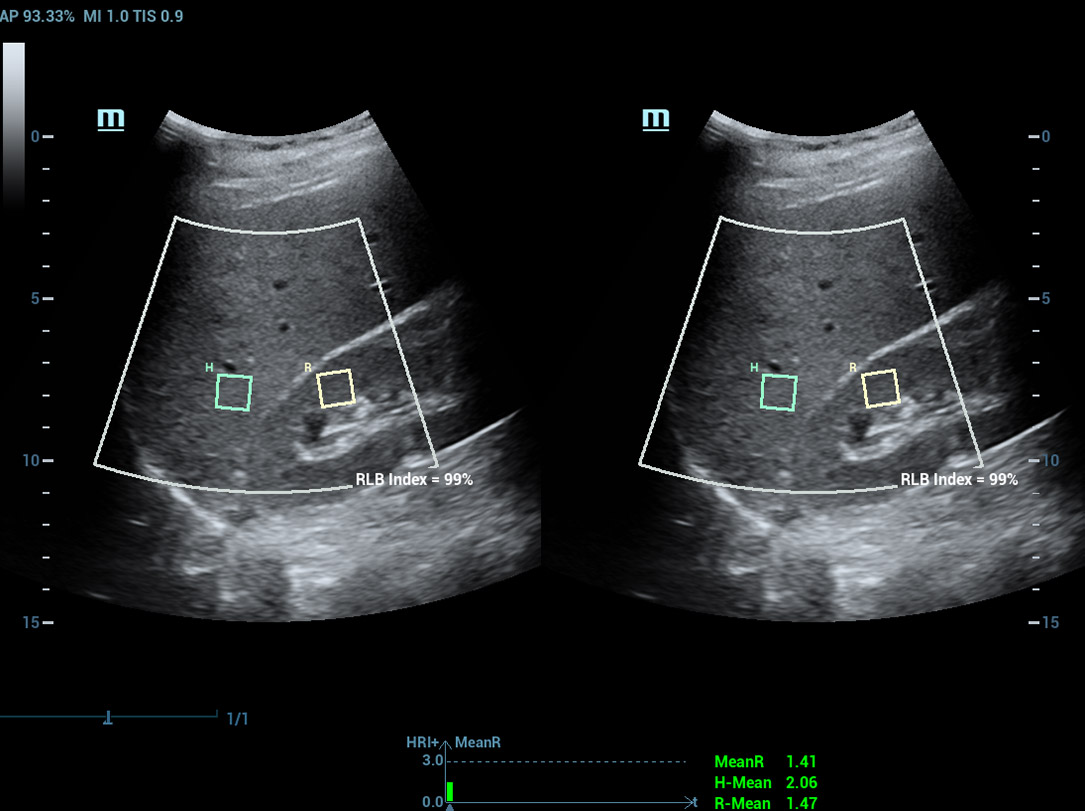

Multi-parametrisch lab voor leververvetting

Een sprong vooruit in het onderzoek naar steatose

Multi-parametrisch lab voor leververvetting

Het multi-parametrische lab voor leververvetting biedt meerdere tools voor kwantitatieve analyse die gebaseerd zijn op verschillende akoestische technologie?n. Het maakt een kwantitatieve analyse van steatose mogelijk en verbetert de gevoeligheid van de detectie van leververvetting in een vroeg stadium.